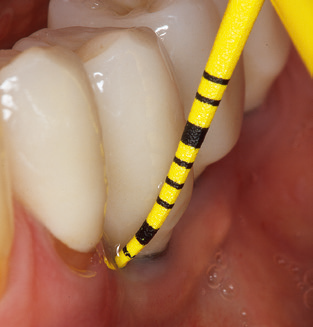

L'aggiornamento della storia medica del paziente è un aspetto importante di SPT e dovrebbe avvenire almeno una volta all'anno. Aiuta il team dentale a identificare e documentare eventuali nuovi fattori di rischio. Soprattutto quando un paziente viene curato per molti anni, è importante stabilire se i fattori di rischio per la salute specifici del paziente e generali sono cambiati. Ciò riguarda principalmente un aumento del rischio a causa del diabete, ma altre condizioni generali (malattie cardiovascolari e neoplasia) possono anche produrre un profilo di rischio modificato a seguito del trattamento eseguito e della somministrazione dei farmaci. Di conseguenza, l'aggiornamento della storia medica come parte di SPT è molto importante, poiché un profilo di rischio modificato può innescare la necessità di adattare l'intervallo di trattamento. Nel passaggio successivo, è importante prestare la dovuta attenzione alla diagnostica. Mentre gli strumenti sono un aspetto centrale di SPT, i risultati e la loro documentazione non devono mai essere trascurati. I risultati parodontologici sono essenziali per una buona diagnosi; aumenti della profondità della tasca e l'indice BOP sono chiari indicatori dell'avanzamento della malattia parodontale e perimplantare. Pertanto, il team non dovrebbe evitare di sondare anche gli impianti, con l'obiettivo di raccogliere i dati richiesti. Allo stesso tempo, è importante utilizzare sonde parodontali con segni millimetrici. Le sonde metalliche sono già state utilizzate per determinare la profondità della tasca attorno ai denti naturali per decenni. Nel caso degli impianti, la sfida di registrare profondità delle tasche corrette e riproducibili è ancora maggiore. Poiché la discrepanza tra il diametro dell'impianto e il contorno della sovrastruttura si traduce regolarmente in un over-contouring della sovrastruttura, le sonde flessibili che presentano ancora marcature millimetriche sono una soluzione sensata per misurare la profondità della tasca attorno agli impianti (ad es. Colorvue Kit PCV11KIT6, HuFriedy; Fig. 4 ).

Fig. 4: Sonde flessibili con marcature millimetriche sono consigliate per il sondaggio di impianti dentali (ad es. Colorvue Kit PCV11KIT6, HuFriedy). - Fig. 5a e b: Un inserto diritto (1P, W&H Dentalwerk Bürmoos GmbH) è uno strumento adatto per l'uso su tutti i denti naturali. - Fig. 6: Inserti curvi (3Pr / 3Pl, W&H Dentalwerk Bürmoos GmbH) si prestano alla lavorazione di aree difficili da raggiungere del dente e delle superfici radicolari (ad es. Forcazioni). - Fig. 7: L'inserto esagonale conico per la pulizia dell'impianto (1I, W&H Dentalwerk Bürmoos GmbH) consente una pulizia atraumatica ed efficace della superficie della corona e del moncone. - Fig. 8: Le curette in titanio e carbonio sono strumenti adatti per la pulizia manuale delle superfici dell'impianto.